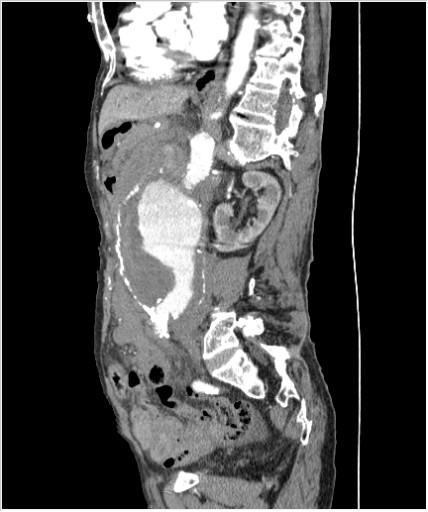

КТ брюшной полости. Мужчина с пальпируемой опухолью в животе

Пациент Т. 64 года, обратился на КТ брюшной полости амбулаторно (!), по направлению семейного врача с диагнозом abdominal mass, буквально: образование брюшной полости.